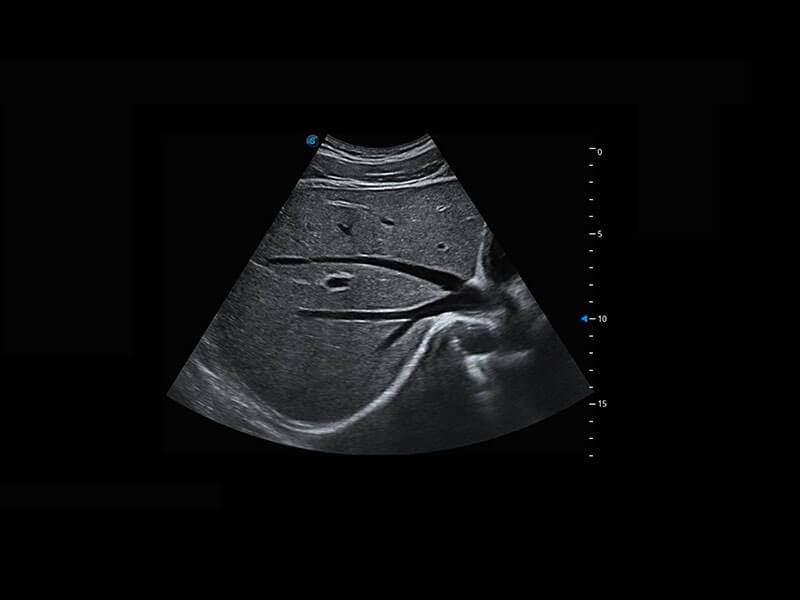

P60提供简单易学易用的高端诊断工具,为您中晚孕筛查提供快速清晰的解剖信息。

S-Fetus能够助您在实时扫查过程中自动识别标准切面、自动测量并录入报告。一个按键,即可快速、高效地获取胎儿生理指标,简化您的产科检查操作。